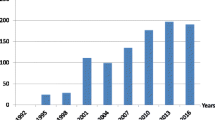

Most cases of cSVD are sporadic, with the age-related and hypertension-related types and CAA being the most prevalent forms. Monogenic cSVD accounts for up to 5% of all causes of stroke [11]. Several causative genes have been identified [12,13,14,15]. Monogenic cSVD, the most common type, is an autosomal-dominant, cerebral arteriopathy characterized by subcortical infarcts and leukoencephalopathy (CADASIL) arising from NOTCH3 gene mutations [16]. Sporadic cSVD has been widely studied whereas monogenic cSVD is still poorly characterized and understood. The majority of cases of both the sporadic and monogenic types, including CADASIL, typically have their onset in adulthood. Forms of the disease manifesting in infancy and childhood are rare, and their diagnosis is often challenging.